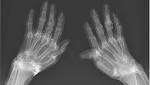

Why a Woman’s Wrists Glowed with Gold Filaments on an X-Ray